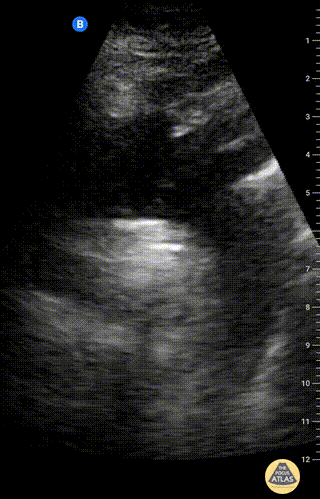

Aorta - Suprasternal view of the aorta

Suprasternal notch view of the aortic arch with brachiocephalic artery (BCA), left common carotid artery (LCA), and left subclavian artery (LSA) branching off. Right pulmonary artery is also visible adjacent to the ascending aorta. Charles Jang, EM PGY-3